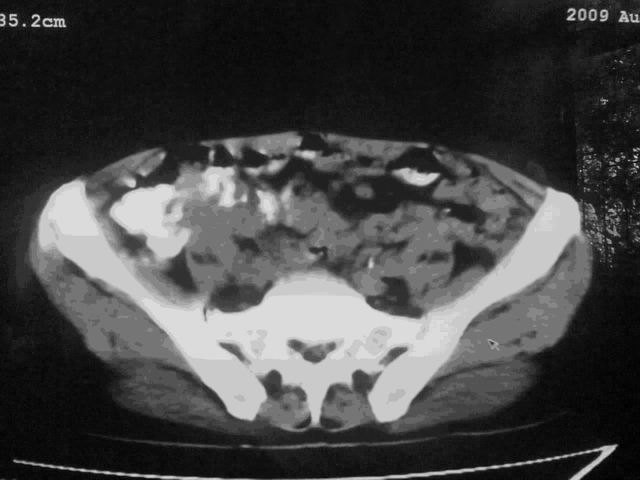

好象是横结肠占位肝转移,胰头占位?【伙计,您的片也真够意思】

伪影太多,考虑降结肠癌伴肝转移,胆囊炎

伪影太多,考虑升结肠癌伴肝转移,胆囊炎

考虑升结肠癌伴肝转移;胆囊炎。

结肠占位并肝及腹膜后淋巴结转移。

明确考眼力!考虑降结肠癌伴肝转移可能性。